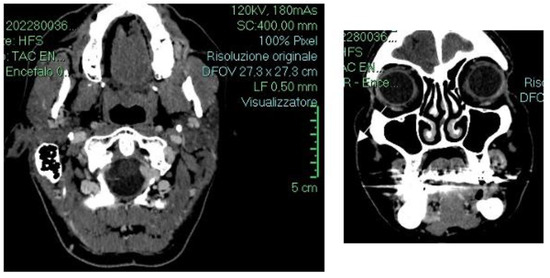

2. Detailed Case Description